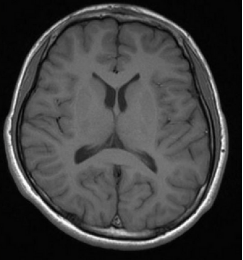

根据陈先生的体格检查,可以发现他有明显运动迟缓、合并有震颤(面具脸、右侧指鼻试验、快速轮替动作、跟膝胫试验缓慢)等帕金森病的典型症状。但为了排除是脑部器质性病变导致的这些症状,我建议陈先生去做一个颅脑的MRI。颅脑MRI(见图1):颅脑平扫未见明显异常,排除颅内占位性病变,符合帕金森的表现。

图1:颅脑MRI平扫未见明显异常。